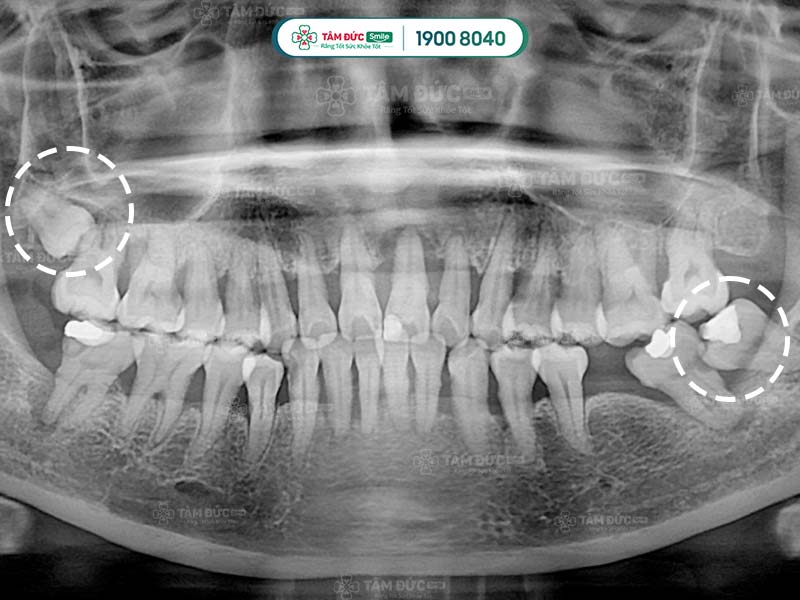

10.1. Chụp phim và tư vấn

Đây là bước quan trọng nhất trong quy trình nhổ răng khôn an toàn. Quý khách cần chụp phim X-quang để bác sĩ xác định vị trí và tư thế của răng khôn. Qua đó, bác sĩ dễ dàng đưa ra phương án nhổ răng an toàn nhất.